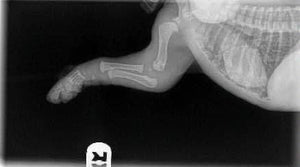

When you get your 8-10 week old puppies, please keep these images in mind. Their bones do not even touch yet. They plod around so cutely with big floppy paws and wobbly movement because their joints are entirely made up of muscle, tendons, and ligaments with skin covering. Nothing is fitting tightly together or has a true socket yet.

* A bit of back-story: This is a baby puppy who had a knock to his elbow and wasn't using it properly, so he was taken to the vet. There is nothing wrong in these x-rays, thankfully it is a soft tissue injury and he is expected to be fine.